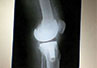

Case 7: Total Knee Replacement

54 years female was suffering from both knee pain for last 4-5 years. She had bilateral advanced osteoarthritis knee.

Patient underwent knee replacement surgery in two stages. 1st right knee was replaced after 8 months left knee was replaced.

X-RAY 1

knee advanced stage of osteoarthritis

X-RAY 2

post op xray after knee replacement